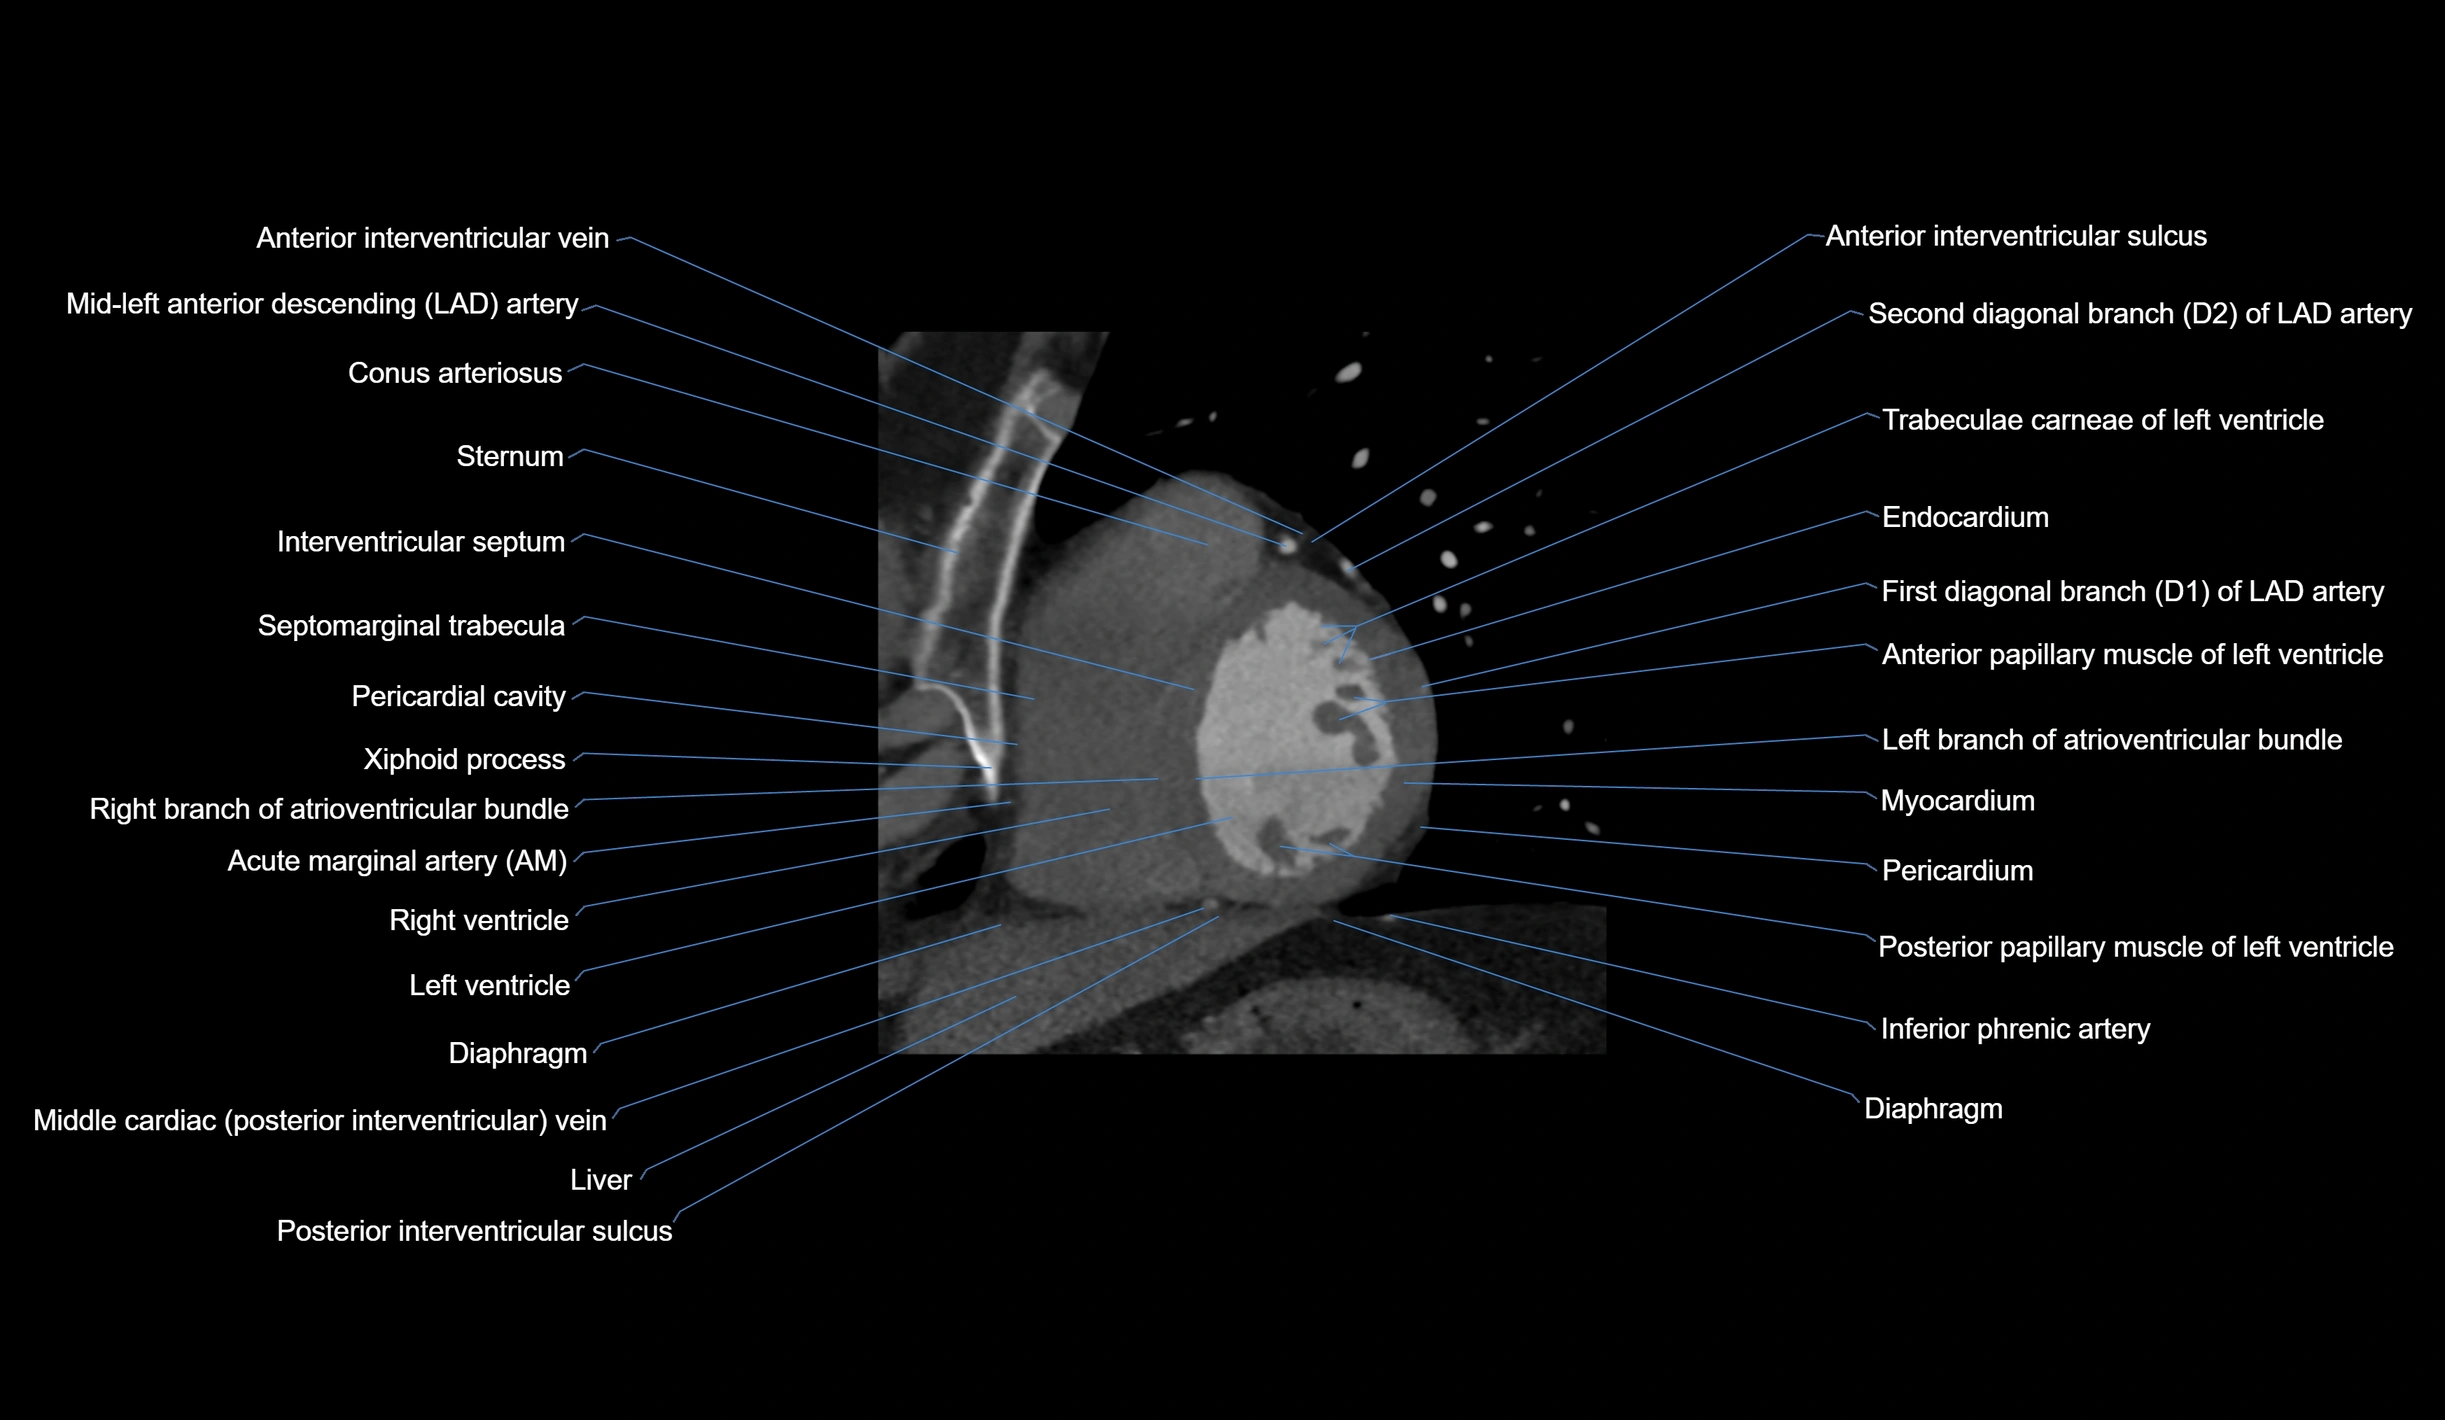

- Acute marginal artery (AM)

The acute marginal artery (AM) is one of the main branches of the right coronary artery (RCA). It typically arises from the mid to distal segment of the RCA and courses along the acute margin (right inferolateral border) of the right ventricle. The AM artery runs within the epicardial fat and supplies blood primarily to the right ventricular free wall.

The number and size of AM branches vary: most individuals have one dominant acute marginal artery, but some may have multiple smaller branches. The vessel is of high clinical importance in right ventricular infarction, since occlusion or disease of the RCA or AM branch can compromise right ventricular contractility and systemic venous return.

CT Coronary Angiography (CCTA):

-

Best non-invasive modality for acute marginal artery visualization

Shows origin, course along the acute margin, and right ventricular branches

Detects stenosis, occlusion, calcified and non-calcified plaques, aneurysm, or anomalous course

Multiplanar reformats and 3D reconstructions help in pre-PCI and surgical planning

Critical for assessing right ventricular infarction risk in RCA disease

CT images